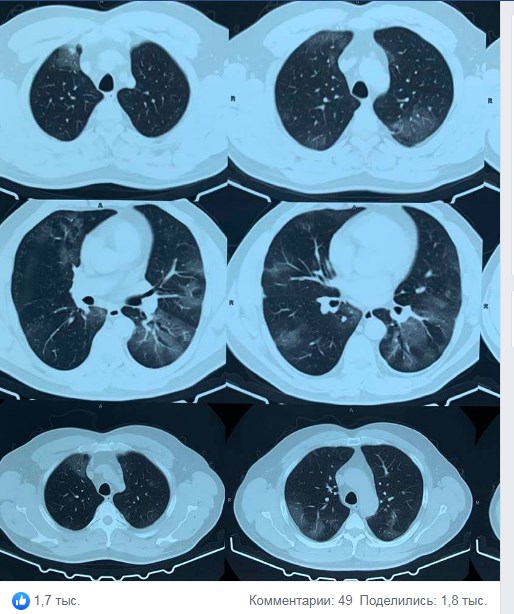

"Кількість хворих з COVID-19 зростає на очах і ми з вами прекрасно розуміємо, що тільки коли збільшиться доступ до тестування ми це побачимо в офіційної статистиці. Вже з аналізу історій хвороби перших пацієнтів можна говорити про деякі особливості перебігу захворювання", - зазначила вона.

Зокрема, за словами доктора, коронавірус найчастіше протікає без кашлю і нежиті.

"Підвищення температури тіла зазвичай до субфебрильних цифр і рідко перевищує позначку в 39 градусів", - уточнила лікар.

Крім того, за її словами, поки хворі з важкими формами не домінують.